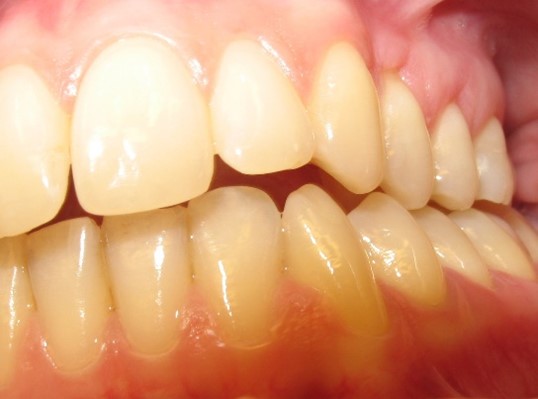

図A. 舌突出による前頭咬合の開き具合が異なる2つの症例